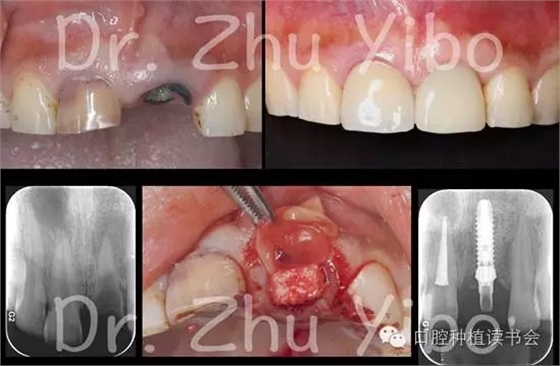

這時(shí),一個(gè)天(feng)才(kuang)的想法在他的腦海中閃現(xiàn),如果拔牙時(shí)保留一部分唇側(cè)的牙根,保留唇側(cè)的牙周膜,能否保存牙槽窩唇側(cè)的束狀骨,同時(shí)不影響植入種植體的骨結(jié)合呢?這個(gè)想法是和之前所有的教科書(shū)格格不入的,一直以來(lái)老師都告訴我們,拔牙要拔干凈,殘留的牙根可能發(fā)生牙根固連、排異反應(yīng)、甚至炎癥。但是理性的思考加上瘋狂的創(chuàng)意產(chǎn)生的是偉大的結(jié)果。動(dòng)物實(shí)驗(yàn)獲得了成功,組織切片證實(shí),保留唇側(cè)部分牙根、即刻種植后3個(gè)月,種植體的骨結(jié)合良好,牙根周?chē)鷽](méi)有炎癥,更重要的是,拔牙窩唇側(cè)骨板沒(méi)有明顯的吸收、改建。之后他的臨床病例自然的也獲得了成功。這是一項(xiàng)了不起的美學(xué)區(qū)即刻種植技術(shù),可以通過(guò)最小的代價(jià),獲得最完美的治療效果,但是卻非常難以推廣,成為新的即刻種植治療方案“金標(biāo)準(zhǔn)”。原因無(wú)外乎幾點(diǎn):操作難度大,技術(shù)要求高,所以能做的醫(yī)生很少,完成的病例也就較少,觀察時(shí)間也較短。1999-2009年就讀于北京大學(xué)口腔醫(yī)院,師從林野教授,獲得種植專(zhuān)業(yè)博士學(xué)位。2009-2012就職于北京大學(xué)口腔醫(yī)院種植中心,任主治醫(yī)師。2012至今就職于北京大學(xué)口腔醫(yī)院第四門(mén)診部從事口腔種植臨床工作。2011年獲得德國(guó)國(guó)家學(xué)術(shù)交流獎(jiǎng)學(xué)金(DAAD)和中國(guó)國(guó)家公派留學(xué)基金,赴德國(guó)海因里希-海涅大學(xué)訪問(wèn)學(xué)習(xí)。2012年赴蘇黎世完成Uli Grunder的美學(xué)種植培訓(xùn)。2013獲得北京大學(xué)口腔醫(yī)院青年科研基金。2014年赴慕尼黑完成Marc Hurzeler的牙周種植培訓(xùn)。2015獲北京大學(xué)口腔醫(yī)院臨床新技術(shù)新療法重點(diǎn)項(xiàng)目支持。2016年赴佛羅倫薩完成P Cortellini和M Tonetti的牙周根面覆蓋與軟組織處理培訓(xùn)。國(guó)內(nèi)多家種植系統(tǒng)講師及同聲翻譯。